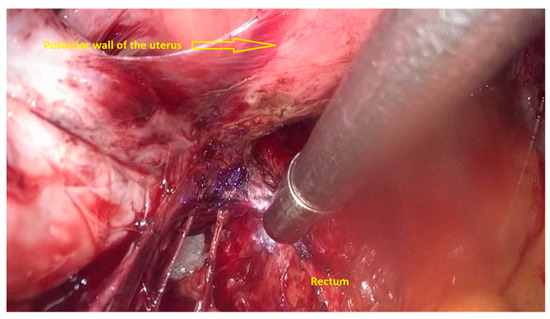

- The deep rectal spaces and rectovaginal septum surrounding the rectal nodule are opened in an anterolateral plan while staying connected to the levator ani muscle and with the preservation of fascia recti (Figure 3).